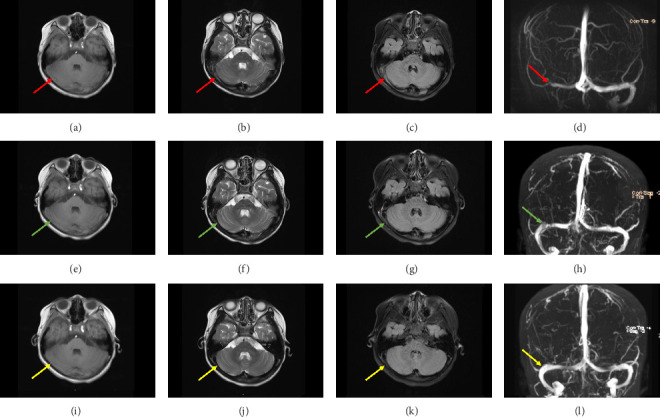

脑静脉窦血栓形成(CVST)在儿童中很少见(占儿童卒中的0.5%-1.0%),与闭合性创伤性脑损伤相关的病例很少。一名七岁女孩在轻度闭合性颅脑损伤后出现神经系统症状。早期CT影像显示了最初被忽视的细微发现,导致诊断延迟。随后的磁共振成像(MRI)和磁共振静脉造影(MRV)证实了CVST的诊断。患者成功地接受依诺肝素桥接治疗,随后接受利伐沙班治疗,实现血栓完全溶解,无出血并发症。本病例强调了儿童创伤后CVST的诊断挑战,其中最初的影像学征象可能被忽视。该研究强调了在持续症状的儿童脑外伤中警惕成像解释的重要性,并证明了新型口服抗凝剂(NOACs),特别是利伐沙班,作为这一人群的治疗选择的有效性和安全性。

Cerebral venous sinus thrombosis (CVST) is rare in children (0.5%-1.0% of pediatric strokes) and uncommonly associated with closed traumatic brain injury. A 7-year-old girl presented with neurological symptoms following a mild closed craniocerebral injury. Early CT imaging revealed subtle findings that were initially overlooked, leading to delayed diagnosis. Subsequent magnetic resonance imaging (MRI) and magnetic resonance venography (MRV) confirmed the diagnosis of CVST. The patient was successfully treated with enoxaparin bridging followed by rivaroxaban, achieving complete thrombus resolution without bleeding complications. This case highlights the diagnostic challenge of posttraumatic CVST in children, where initial imaging signs may be overlooked. It underscores the importance of vigilant imaging interpretation in pediatric brain trauma with persistent symptoms and demonstrates the efficacy and safety of novel oral anticoagulants (NOACs), specifically rivaroxaban, as a therapeutic option in this population.